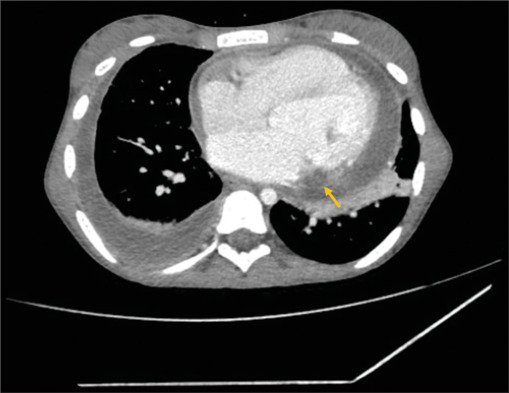

一名13岁女孩在因骨髓炎住院治疗后发生先天性二尖瓣感染性心内膜炎(IE)。临床过程中并发心肌内脓肿和严重的二尖瓣反流。嗜麦芽窄养单胞菌血培养呈阳性,这是一种罕见的IE病因,已知对用于治疗IE的一线药物具有耐药性,并有引起心肌脓肿的倾向。因此,对嗜麦芽葡萄球菌引起的心内膜炎的认识提高是有必要的。

A 13-year-old girl developed infective endocarditis (IE) on the native mitral valve after hospitalization for osteomyelitis. The clinical course was complicated by intramyocardial abscess and severe mitral regurgitation. Blood cultures were positive for Stenotrophomonas maltophilia, a rare cause of IE, which is known to be resistant to the first-line agents used for the treatment of IE, and has a propensity to cause a myocardial abscess. Hence, an increased awareness regarding endocarditis due to S. maltophilia is warranted.